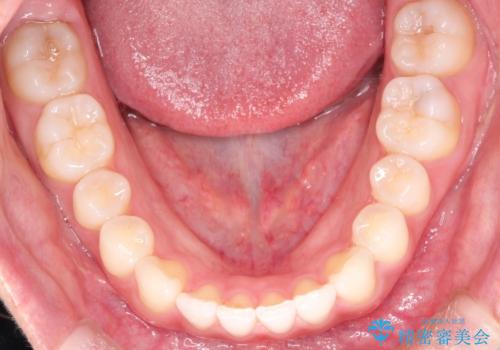

すきっ歯のインビザラインによる目立たない矯正

- すきっ歯を治したいとのことで来院されました。

上下ともに前歯に隙間がありました。

目立たない装置をご希望のためインビザラインで矯正治療を行うこととしました。

使用時間を守っていただけたので、スムーズに治療を終わることができました。